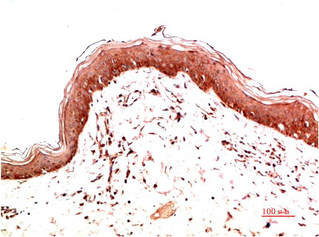

分类: 科研抗体货号: P43463别名: UBC16; UBC-16应用: WB,IHC反应种属: Human,Rat